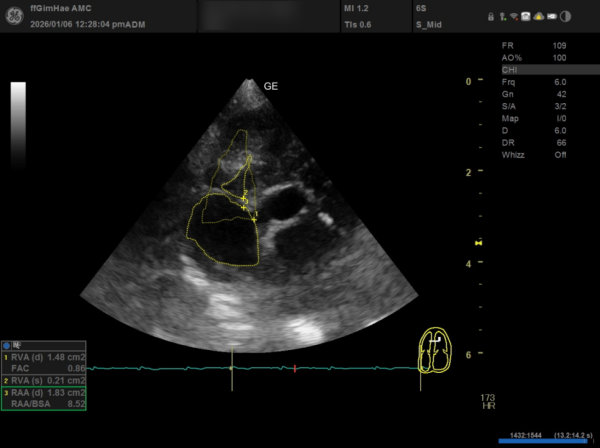

④ RA(우심방) 확장

RAA/BSA: 8.52로 우심방의 유의미한 확장이 확인되었습니다.